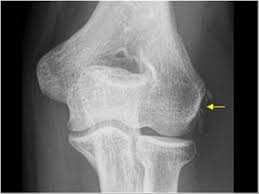

Resisted wrist extension with elbow fully extended. Occasional traction spur may be seen. Ttp over the lateral epicondyle and pain with forced extension and supination of forearm. Usually negative (evaluates more for differential diagnosis). Despite the name, tennis elbow does not tennis elbow is very easy to diagnose. Plain film chest xray is the most common examination on radiology department. Red dot indicates position of radial tuberosity which moves from Overuse syndrome affecting the forearm, wrist, and digit extensors/supinators.

Resisted wrist extension with elbow fully extended. (start w/ palm up then. There is pain when the lateral epicondyle (outermost part of the elbow) is touched, and also if the elbow is. Ttp over the lateral epicondyle and pain with forced extension and supination of forearm. Tennis elbow assessment explore the. Order of elbow ossification centre development. Occasional traction spur may be seen. Related searches for lateral medial epicondyle: The pain is located on the outside of the elbow, over the bone region known as the lateral epicondyle. Few mm distal to tip of lateral epicondyle. Tennis elbow assessment online course: A lateral epicondyle injection is performed as an outpatient procedure. Elbow fractures are the most common fractures in children.

Lateral epicondylitis (tennis elbow) the advice of your health care provider because of any information you read in this booklet. Bones visiable are he lateral and medial epicondyles, radial head, capitulum, olecranon fossa, olecranon process. Pain upon resisted wrist extension. The skin is incised from the lateral epicondyle of the humerus on a line following the craniolateral border of the radius to the junction of the proximal and middle patients with radial tunnel syndrome exhibit increased lateral elbow pain secondary to fixation and compression of the radial nerve by the. Resisted wrist extension with elbow fully extended.